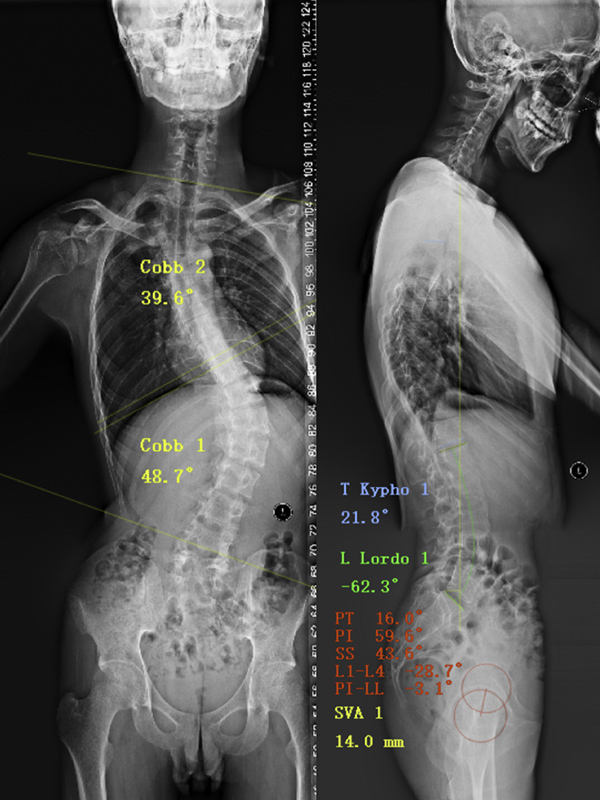

·Radiographic imaging 影像学检查

患者术前冠状面失衡严重

脊柱侧弯(图1)是一种脊柱出现异常弯曲和旋转的疾病,主要诊断标准是在正位 X 线平片上脊柱弯曲度即Cobb角超过10°(图2)。脊柱侧弯可能由先天性、神经肌肉型、退变性等多种原因导致,当无法确定其他病因时,被称为特发性脊柱侧弯。特发性脊柱侧弯是最常见的类型,占总数的75%~85%[1]。

脊柱侧弯的解剖结构复杂,结构重叠,X线检查是脊柱侧弯的首选检查方法,从X线片上,可以获得许多重要信息:侧凸的原因、分类以及弯度、部位、旋转、骨龄、代偿度等。X线的优势在于测量脊柱侧弯的cobb角,而CT和MRI检查更能清晰的反应脊柱侧弯的整体和细微结构,对于准备手术的患者,MRI检查、螺旋CT扫描及三维重建是不能缺少的检查方法。研究认为三维CT重建可以在其中50%的患者中发现潜在的异常结构[2]。